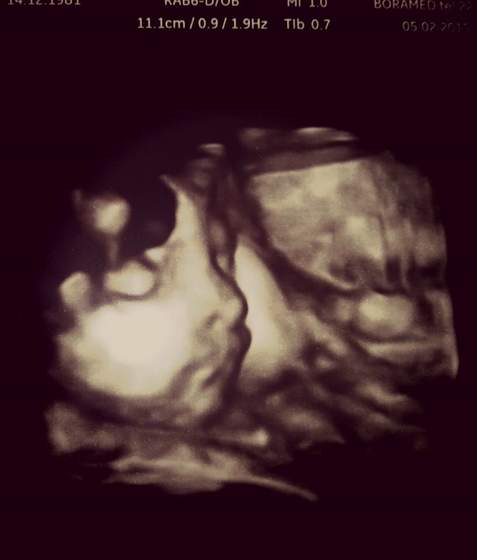

rurka napisała smsa że w sobotę zaczyna 36ty tydzień, torby ma już spakowane, skurcze już miewa nieregularne, ale na razie jest spokojna. Trzyma za nas kciuki i pozdrawia